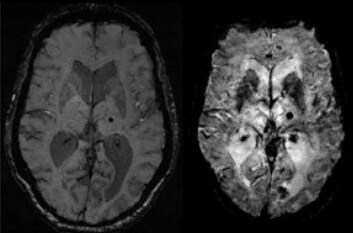

Рис 1. Изображение, полученное с использованием новой методики сканирования PADRE (справа), показывает более высокую чувствительность к микро кровоизлияниям, чем классическая SWI (слева).

Цель: Апробация и внедрение в клиническую практику новейших техник SWI, основанных на комбинированном использовании фазовых и магнитудных изображений высокого разрешения для управления контрастом МР изображения. Описание проекта: Методика SWI (Susceptibility-weighted image) представляет особый тип контраста в МРТ изображениях, основанный на различной магнитной восприимчивости разных тканей [1]. Данная методика высокочувствительна к присутствию в тканях атомов железа, которое входит в состав гемоглобина крови, что позволяет использовать методику для обнаружения патологий кровоснабжения [2], микрокровоизлияний при травме мозга [1,3], и оценки накопления железа в тканях мозга при нейродегенеративных заболеваниях [4-8]. При черепно-мозговой травме выявление диффузных аксональных повреждений и микрокровоизлияний являются критически важным для планирования и прогнозирования терапии. Новая импульсная последовательность PADRE [9], основанная на технике смещенного эхо PRESTO, позволяет комбинировать магнитудные и фазовые изображения, что улучшает разрешение изображения и отношение контраст/шум [10]. Задачей проекта является исследование диагностической чувствительности методики и ее сравнение с техниками T2*GRE и VienBold. Результаты: Методика обеспечивает более высокую чувствительность к микроскопическим повреждениям мозга за счет нового типа контраста, и более высокого разрешения по сравнению со стандартными методиками.